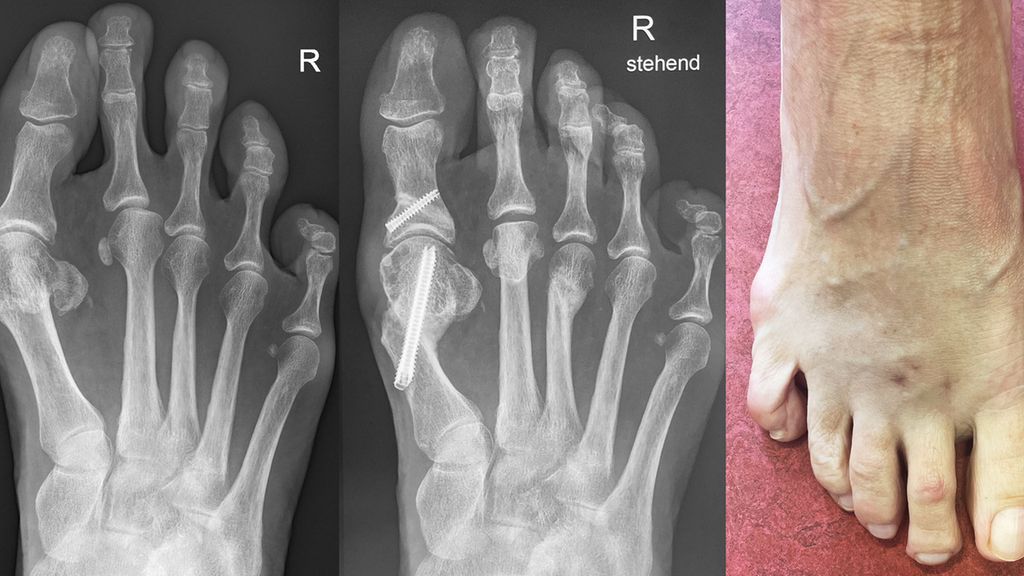

Unter der Generation 3 werden Modifikationen der Chevron-Osteotomie zusammengefasst, die per Stichinzision mittels Fräse durchgeführt werden. Fixiert wird mit kopflosen Schrauben. Redfern und Vernois bevorzugen hier sehr lange 3,5 mm- bzw. 4,0 mm-Schrauben, die von proximal medial am Metatarsale 1 in das Köpfchen eingebracht werden.2 Gerhard Kaufmann führt ebenfalls eine Osteotomie mit Fräse durch, fixiert aber weiter distal ähnlich wie bei der klassischen Chevron-Osteotomie (Abb. 1).

Vernois und Redfern präsentierten 100 Füße mit einem von 95% der Patienten als sehr gut und gut beurteilten Outcome.2 Gerhard Kaufmann publizierte 2020 seine Ergebnisse der minimalinvasiven Chevron-Osteotomie im Vergleich zur offenen Chevron-Osteotomie,6 mit Kontrollen nach 6 und 12 Wochen sowie 9Monaten und 5Jahren. Es gab keine Korrekturverluste zwischen den kurzfristigen und langfristigen Kontrollen, der Vergleich der Gruppen ergab keine Unterschiede. Jowett und Bedi analysierten 2017 die Lernkurve der minimalinvasiven Chevron-Osteotomie.7 Sie stellten eine steile Lernkurve fest. Palmanovich beschrieb 27 Patienten als notwendig, um die Lernkurve zu verlassen.8 Wenn die Technik beherrscht wird, so sind auch schwere Hallux-valgus-Fehlstellungen korrigierbar und vor allem Wundkomplikationen sind selten.

Auch die Akin-Osteotomie kann sehr einfach minimalinvasiv durchgeführt werden. Sie wird entweder mit einer Schraube oder aber einfach mit Tapes für 4 Wochen stabilisiert (Abb. 2).